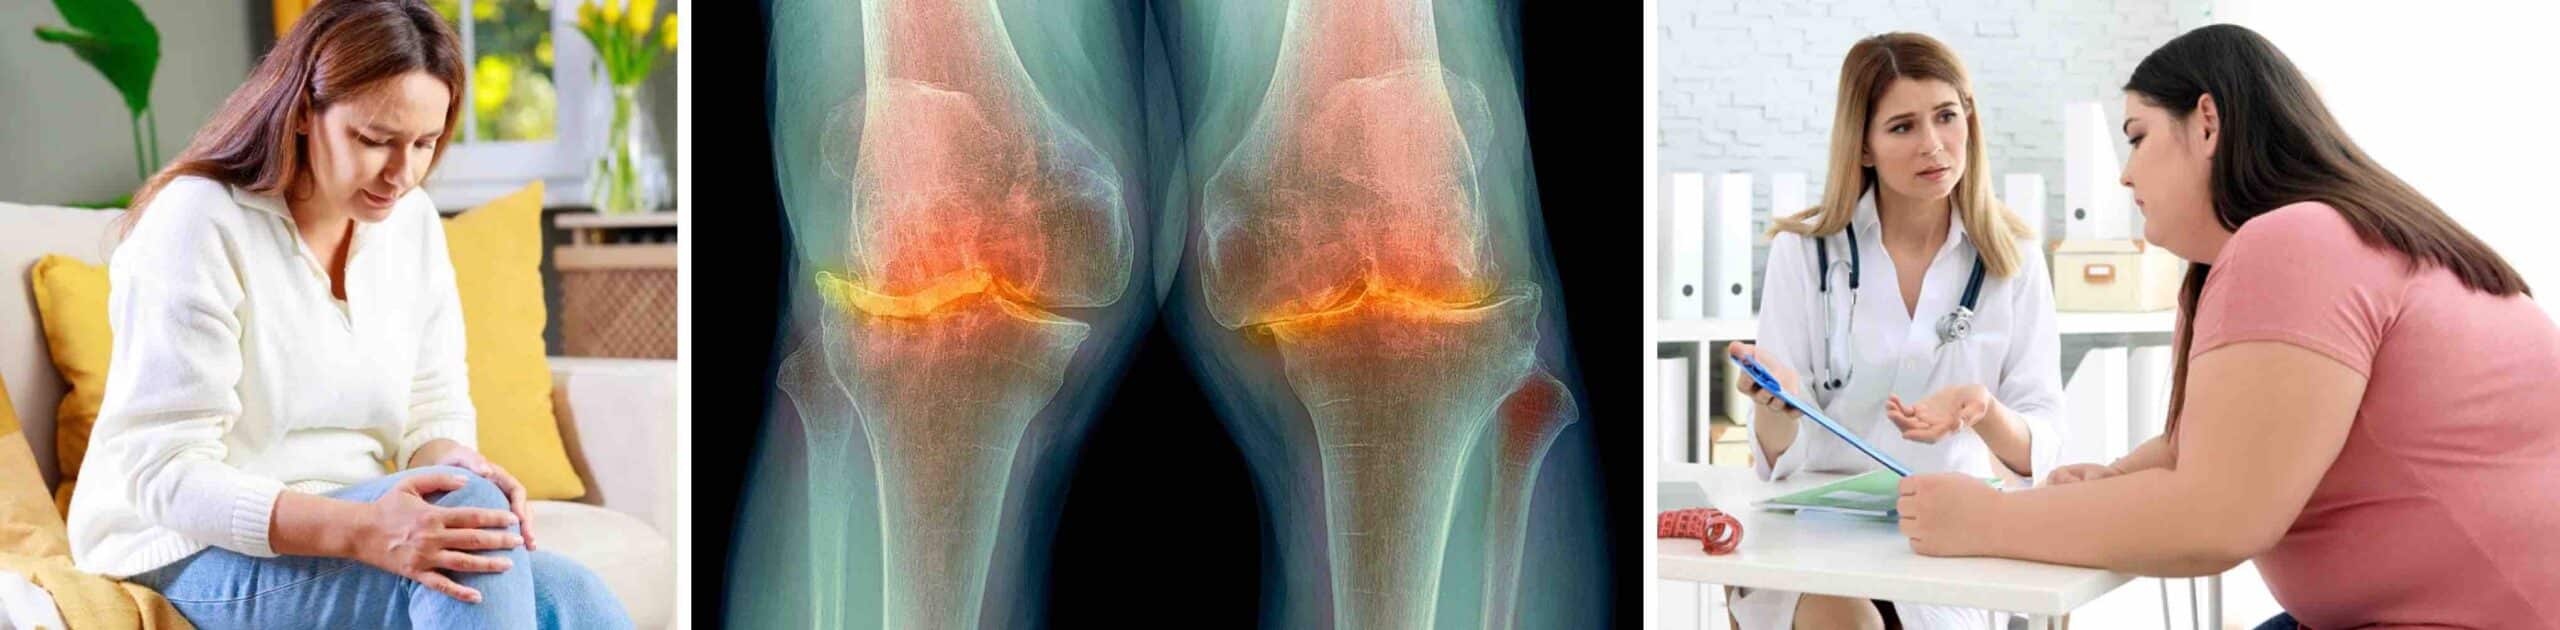

ARTROSE DO JOELHO

O sobrepeso é o fator número um para o agravamento da artrose do joelho, doença caracterizada pela degeneração da cartilagem. Cartilagem é o tecido branco e brilhante que recobre os ossos dentro das articulações. O desgaste da cartilagem pode deixar os ossos que se articulam em contato direto, provocando sintomas como dor, inchaço, crepitação, deformidade e limitação funcional. O grande problema da artrose é que a cartilagem não se regenera. O desgaste da cartilagem é irreversível. Quem tem artrose no joelho precisa obrigatoriamente cuidar do peso corporal e mantê-lo dentro da faixa de normalidade para não aumentar o desgaste da cartilagem. Para quem está com o peso acima do normal, o ideal é fazer a sua diminuição de maneira natural, sem necessidade de medicamentos ou de uma cirurgia bariátrica. Essas abordagens podem ser indicadas para casos de obesidade extrema. A maioria das pessoas consegue diminuir o peso corporal de forma natural.